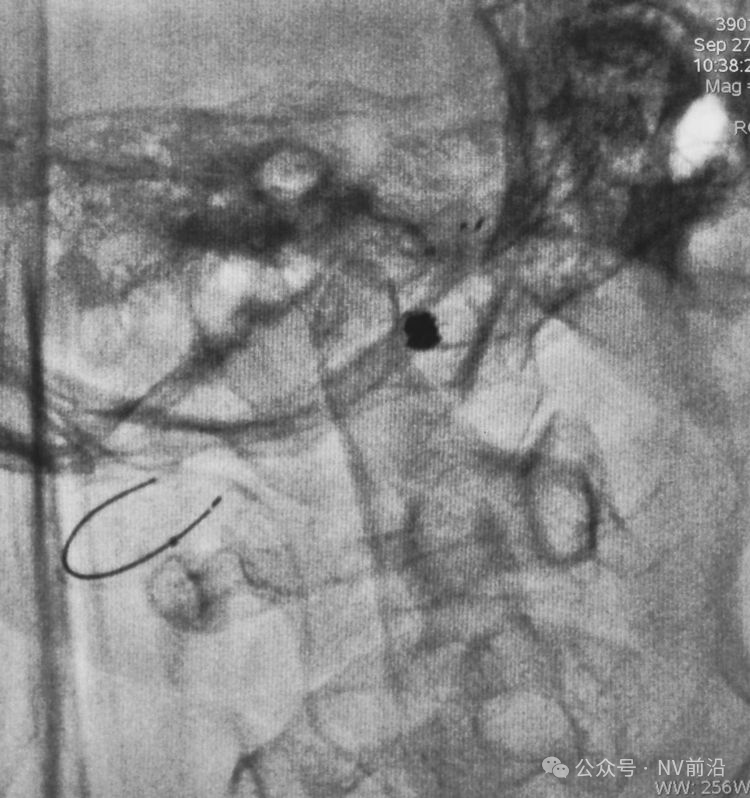

依次送入QC-2-4-3D,2-3-Helix,1.5-2-Helix,1.5-2-Helix四枚弹簧圈,最后一枚弹簧圈将管头(箭头)顶出瘤腔。

将Traxcess 14微导丝送入微导管,稍向远心端送微导管,使管头远离动脉瘤,再缓慢撤离。